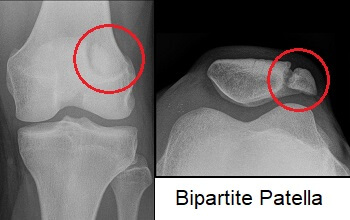

How do you distinguish a bipartite patella from a fracture?

Smooth edges and location at the upper lateral patella.